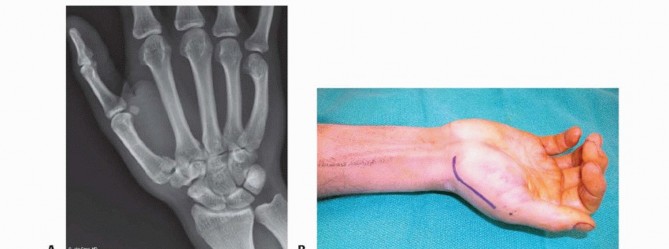

Clinical Evaluation and Diagnostic Imaging

The clinical evaluation must begin with a detailed history, focusing on the mechanism of injury, occupational demands, and hand dominance. Physical examination will typically reveal profound localized tenderness, swelling, and ecchymosis around the thenar eminence. Palpable instability or a visible "shelf" deformity at the CMC joint strongly suggests dorsal subluxation of the metacarpal shaft. A rigorous neurovascular examination is mandatory, with specific attention paid to the superficial radial nerve and the palmar cutaneous branch of the median nerve, both of which are at risk during surgical approaches to this region.

Our imaging protocol must be exhaustive to provide a three-dimensional understanding of the fracture morphology. Standard hand radiographs are insufficient due to the unique 30-degree pronated position of the thumb relative to the rest of the carpus. A True AP View of the Thumb CMC Joint (Robert's view) is obtained with maximal forearm pronation, placing the dorsum of the thumb flat on the cassette. This optimizes visualization of the joint space and the critical ulnar fragment. The True Lateral View (Billing and Gedda) is achieved with the hand pronated 20 degrees and the thumb flat on the cassette, with the X-ray beam tilted 10 degrees from vertical in a distal-to-proximal direction.

Image

For complex, multi-fragmentary Rolando fractures, a Traction View under fluoroscopy is indispensable. Distraction at the CMC joint utilizes ligamentotaxis to help delineate comminuted fragments and assess the potential for closed reduction and percutaneous pinning versus the absolute need for open plating. Furthermore, when plain films inadequately delineate the spatial orientation of fracture fragments, particularly in Zone 2, a high-resolution Computed Tomography (CT) scan is strictly indicated. 3D reconstructions are invaluable for preoperative templating, allowing the surgeon to precisely map screw trajectories and select appropriate plate morphology before entering the operating theater.